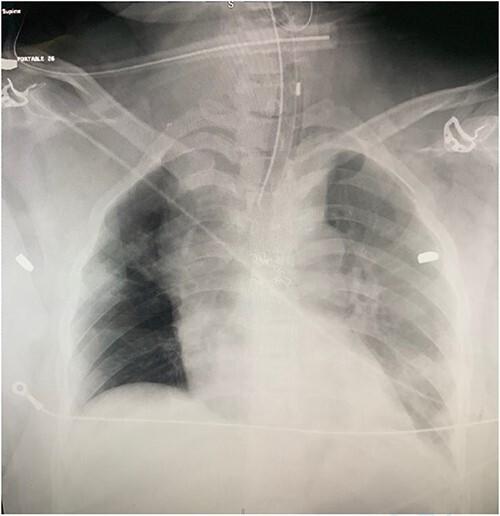

Gunshot wound causing thoracic aortic injury with bullet embolization to the common femoral artery.

Gunshot Wound to the Right Superior Pulmonary Vein With Bullet Embolization to the Aortic Bifurcation: Emergent Surgical Repair.

Arterial Bullet Embolization Secondary to Direct Cardiac Injury in Penetrating Chest Trauma: A Rare Challenging Case Report.